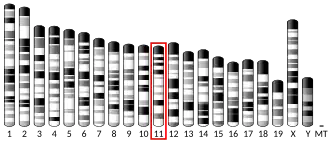

ERBB2, a known proto-oncogene,[11] is located at the long arm of human chromosome 17 (17q12).[12]

FISH can be used to measure the number of copies of the gene which are present and is thought to be more reliable than immunohistochemistry.[47] It usually uses chromosome enumeration probe 17 (CEP17) to count the amount of chromosomes. Hence, the HER2/CEP17 ratio reflects any amplification of HER2 as compared to the number of chromosomes. The signals of 20 cells are usually counted.